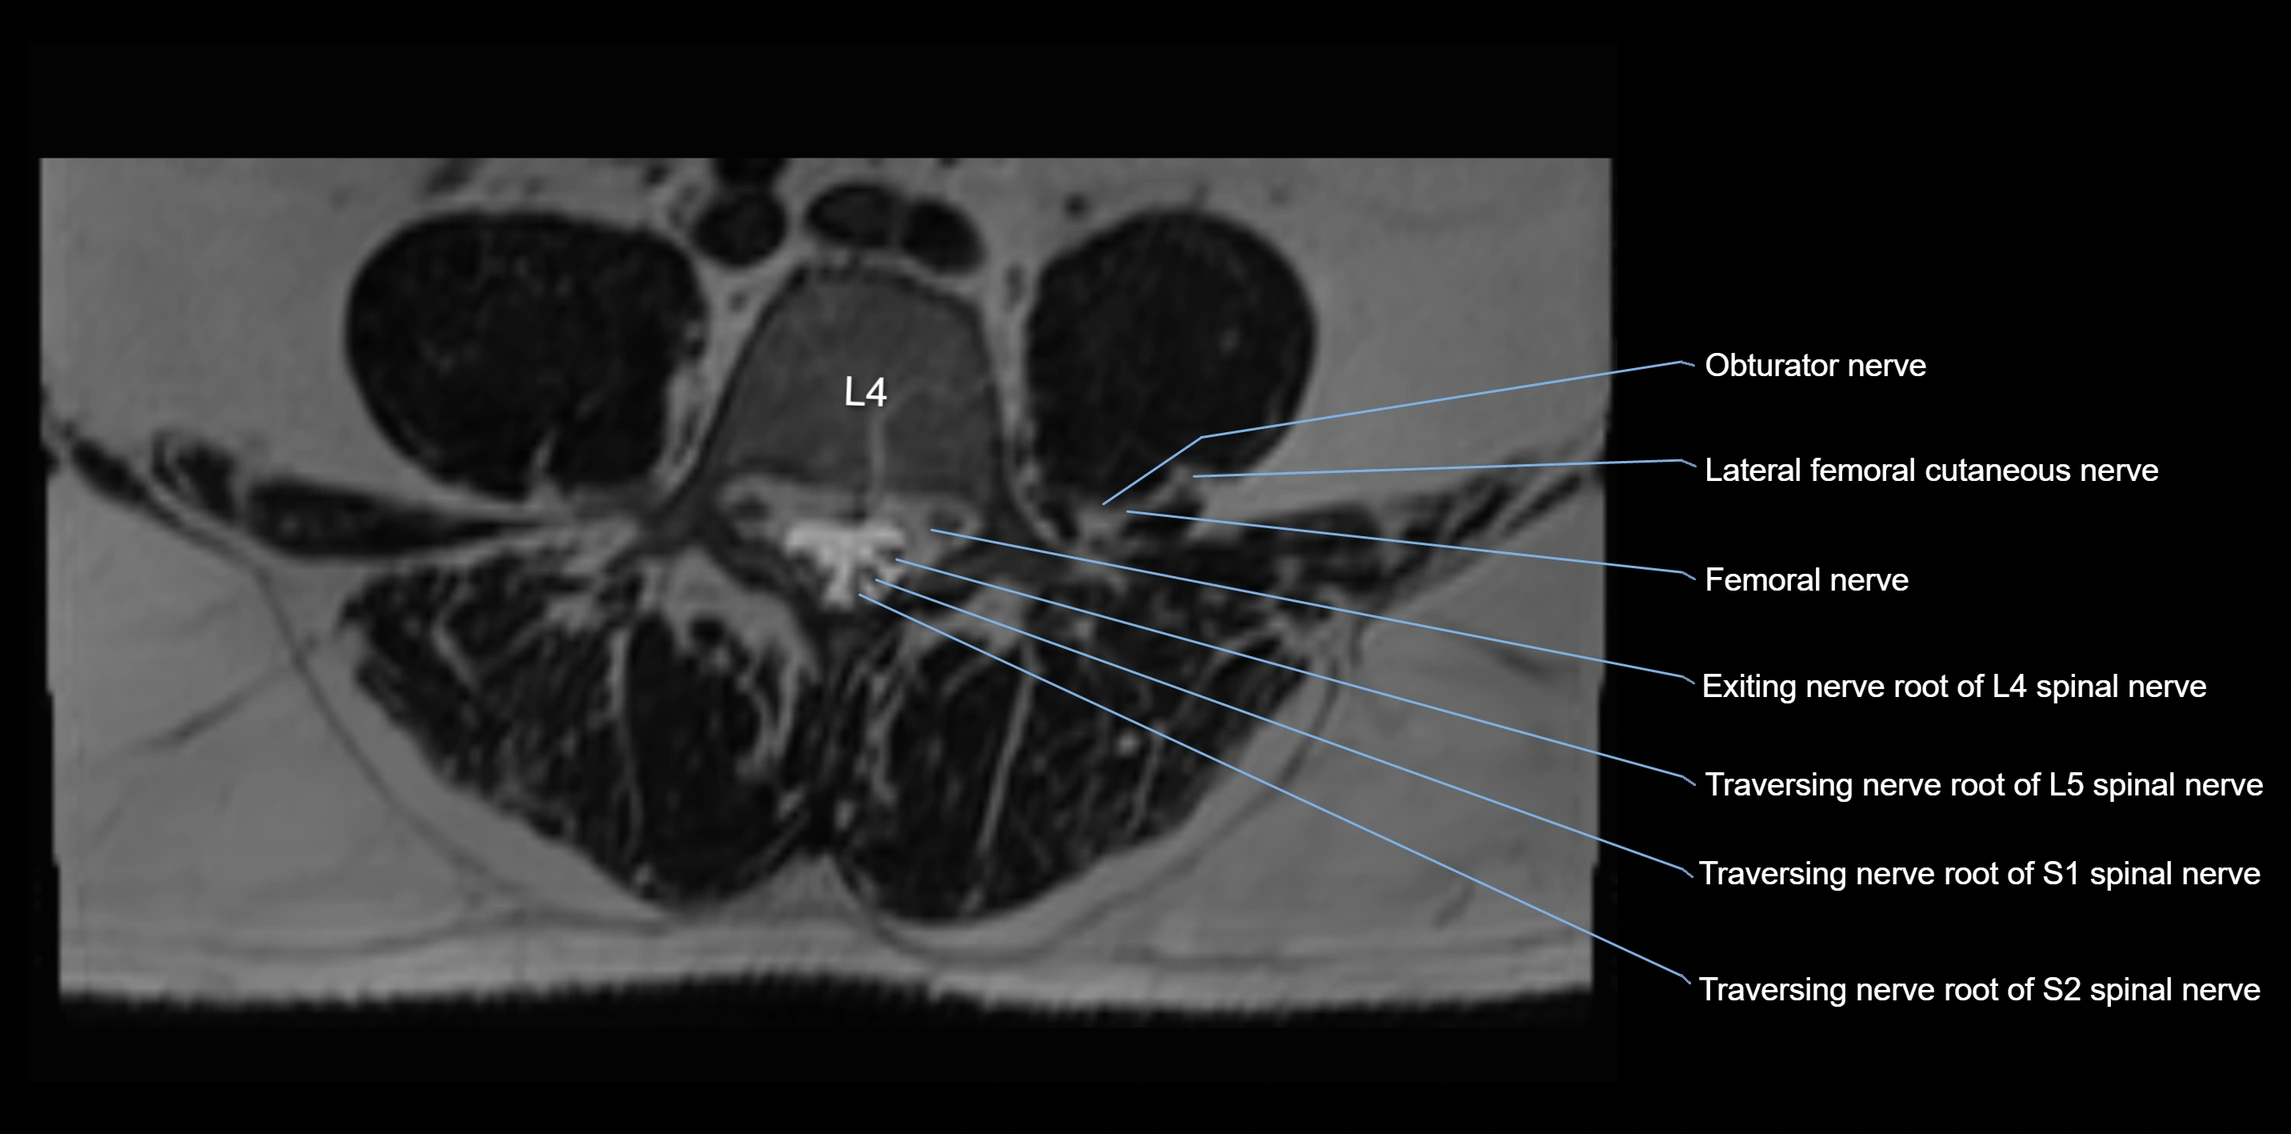

MRI Appearance

T1-weighted images:

• Nerve appears as a very thin low-to-intermediate signal intensity structure

• Surrounded by bright fat, aiding visualization

T2-weighted images:

• Nerve shows intermediate to mildly hyperintense signal compared to muscle

• Pathological involvement appears brighter

STIR (Short Tau Inversion Recovery):

• Normal nerve appears dark

• Inflamed or entrapped nerve appears bright hyperintense

T1 Fat-Sat Post-Contrast:

• Normal nerve enhances minimally

• Pathologic nerve (neuritis, entrapment, tumor infiltration) shows focal or diffuse enhancement

3D T2 SPACE / CISS:

• Nerve appears intermediate to mildly hyperintense compared to muscle

• Surrounded by bright fat or CSF, improving visualization

• Best sequence for mapping small pelvic nerves such as the anococcygeal

MRI image

image